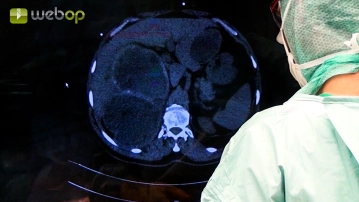

Evaluación de hallazgos; Adhesiolisis; Preparación libre del periquiste extrahepático en el lóbulo izquierdo del hígado

Ajustes de sonido Por lo general, los quistes muestran adhesiones masivas al entorno. En primer lugar, se disecan las adhesiones del quiste del lado izquierdo al epiplón. Debe evitarse estrictamente la apertura accidental de los quistes. A continuación, se observa que el periquiste está adherido al antro gástrico. Estas adherencias se liberan ahora de forma gradual, en parte mediante la colocación de pinzas de Overholt.